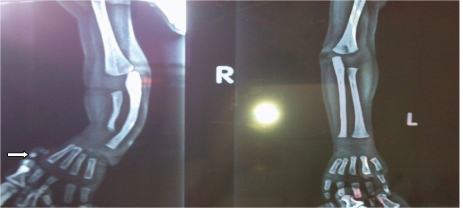

Initial laboratory investigations gave the following results: complete blood count: hemoglobin, 7 g/dL; corrected reticulocytic count, 3 %; total leukocytes count (TLC): 12600/uL, differential count revealed 55% neutrophils, 38% lymphocytes, 5% band cells (Immature neutrophils), eosinophil and monocytes 1% each, platelet count, 18,000/uL; Coagulation profile - prothrombin time, 14 sec (control 13 sec); partial thromboplastin time, 30 sec (control 30). Liver function test had the following results: total serum bilirubin 7.5 mg/dL; Indirect serum bilirubin 7.1 mg/dL (direct), 0.4 mg/dL; and serum glutamic pyruvic transaminase (SGPT) 28 U/L. Serum Electrolytes, Serum C reactive protein (CRP) and kidney function were within normal limits. TORCH screens were normal. Bone marrow aspiration cytology was not done because parents did not given consent for bone marrow aspiration cytology. Skiagram of the forearm showed dysplastic radius, curved ulna and absent first metacarpal bone of right hand and only two dysplastic phalangeal bone (white arrow) of right thumb [Table/Fig-2]. Ultrasongraphic study of his abdomen and brain were normal. On the basis of clinical presentation, physical findings, isolated thrombocytopenia, and X-ray results, the diagnosis of TAR syndrome with atypical presentation was made. Patient was managed in our hospital with packed cell transfusion at rate of 10 ml /kg two times on alternate day and two units platelets concentrates transfusion, Intra-venous antimicrobials, and other supportive treatment. He gradually improved and on day 3 of admission became asymptomatic and discharged after seven days of hospital stay with advice to consult orthopedic surgeon for opinion regarding limb reconstruction and echocardiogram to rule congenital heart disease. In follow up for past one month, he had gained weight 1kg, without any new bloody diarrhoeal episode, bleeding manifestation and his echocardiogram was normal.

Skiagram of the both forearm showing dysplastic radius, curved ulna and absent first metacarpal bone of right hand and only two dysplastic phalangeal bone (white arrow) of right thumb